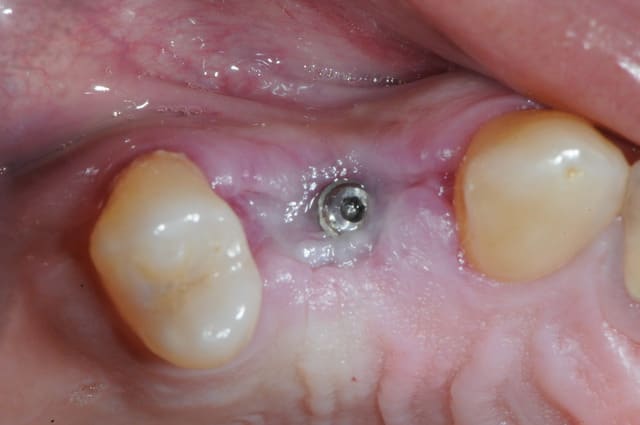

dis moi la tu le trouves comment mon compromis avec l'espace biologique

eii

d'après toi faites il y a combien de temps?

Superbe ratrapage suite à une operculisation d'une vis de couverture. Félicitations. Je te savais costaud béotien mais là tu m'impressionnes vraiment.

- pas de vis de couverture , pas d'operculisation!!

Même pas de lambeau pédiculé palatin!

Wouaww les photos beotien !! Quel progrès ! Super !

Oui c'est bon l'humour en fin de semaine. Content que tu le comprennes.

Félicitations sincères, beau résultat.

Surtout n'arrête pas de mettre des photos!